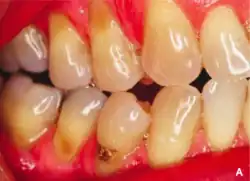

Abrasion is the non-carious, mechanical wear of tooth from interaction with objects other than tooth-tooth contact.[1] It most commonly affects the premolars and canines, usually along the cervical margins.[2] Based on clinical surveys, studies have shown that abrasion is the most common but not the sole aetiological factor for development of non-carious cervical lesions (NCCL) and is most frequently caused by incorrect toothbrushing technique.[3]

Abrasion frequently presents at the cemento-enamel junction and can be caused by many contributing factors, all with the ability to affect the tooth surface in varying degrees.[4]

The appearance may vary depending on the cause of abrasion, however most commonly presents in a V-shaped caused by excessive lateral pressure whilst tooth-brushing. The surface is shiny rather than carious, and sometimes the ridge is deep enough to see the pulp chamber within the tooth itself.

Non-carious cervical loss due to abrasion may lead to consequences and symptoms such as increased tooth sensitivity to hot and cold, increased plaque trapping which will result in caries and periodontal disease, and difficulty of dental appliances such as retainers or dentures engaging the tooth. It may also be aesthetically unpleasant to some people.[3]

Abrasion occurring on the cervical margins from the effects of friction from toothbrushing and abrasive toothpastes